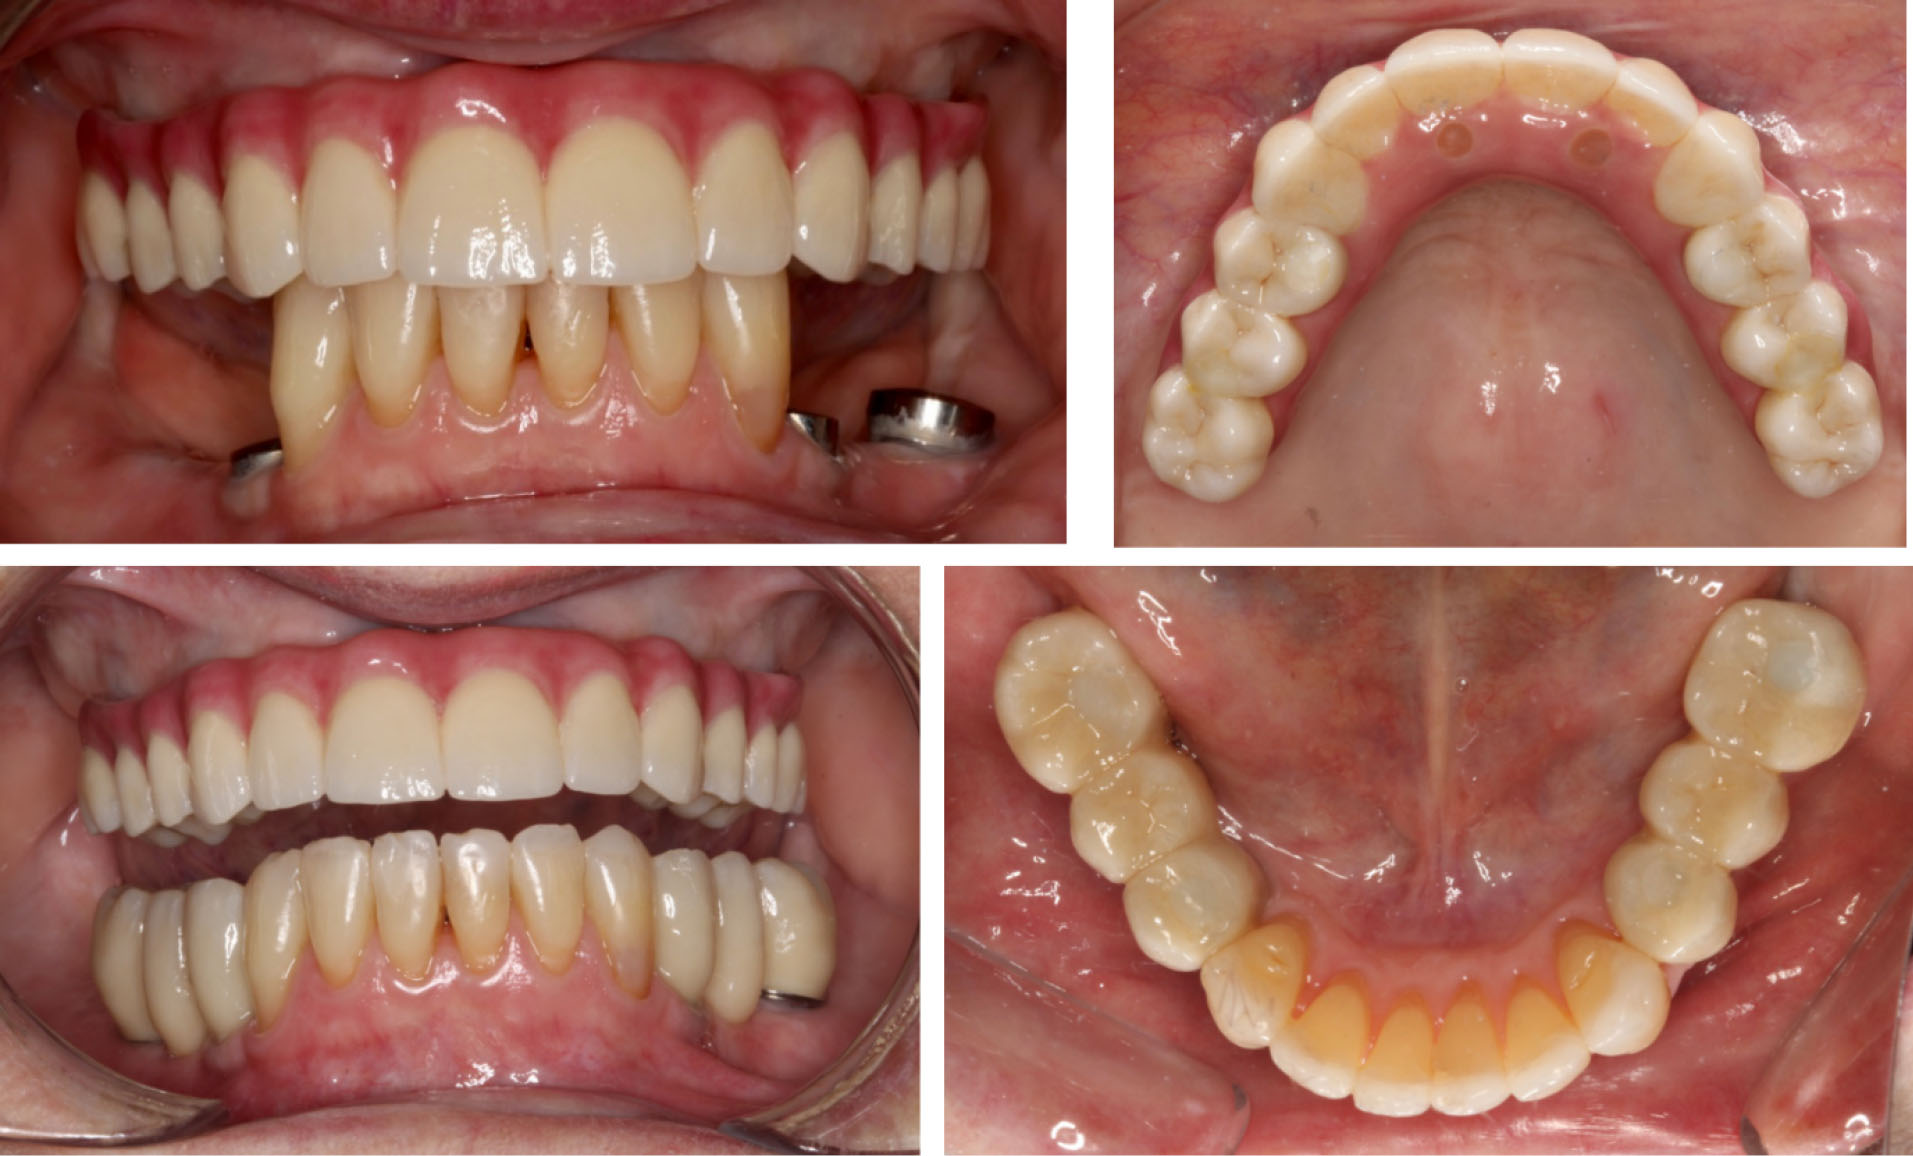

Screw-retained abutments were tightened before the installation of the definitive screw-retained prosthesis according to the manufacturer’s recommendation. Screw-access channels were sealed and restored using dental polytetrafluoroethylene (Teflon) tape and composite resin ().

joddd-15-115-g008

Figure 8. Final maxillary and mandibular all-ceramic screw-retained prostheses.

The mandibular implant-supported fixed partial dentures were fabricated following similar fabrication steps concomitantly to the fabrication of the maxillary prosthesis. The impression technique also used open custom tray with implant abutments joined with light-cured resin to prevent distortions. The incisal edge anatomy of anterior teeth was reestablished with direct composite restorations before taking the final impression. These restorations increased the OVD slightly without compromising comfort and function. The mandibular prostheses were also milled in highly translucent zirconium oxide and layered with tooth-color porcelain (). However, these differed from the maxillary prosthesis in that the occlusal surfaces were in zirconia, and the mandibular fixed partial dentures had the occlusal surfaces in a layering ceramic (IPS e.max Ceram ZirLiner, Ivoclar Vivadent, Australia) in order to create a softer occlusal contact surface () as zirconia tends to wear more the opposing tooth. 11

This case report describes the oral rehabilitation of a patient with a compromised dentition and missing mandibular and maxillary teeth who wanted to improve comfort, masticatory function and aesthetics. A maxillary full-arch fixed ceramic prosthesis and mandibular ceramic fixed partial dentures, all supported by implants placed via guided surgery, were used to replace the missing teeth in a predictable manner. The planning and delivery of the treatment was facilitated and optimized with the aid of digital technologies. All the steps were planned to minimize the risk of errors and complications during both the implant placement and fabrication of the final prostheses, thus reducing the numbers of clinical sessions and the cost associated with repetitions. Hence, the success of the case () shows that a thorough clinical examination guiding the treatment plan, followed by the combination of digital and conventional workflows that facilitate the communication between clinician and dental technician, provide a predictable treatment outcome in implant rehabilitation of the edentulous maxilla.

joddd-15-115-g009

Figure 9. Six-month postoperative smile – anterior view.